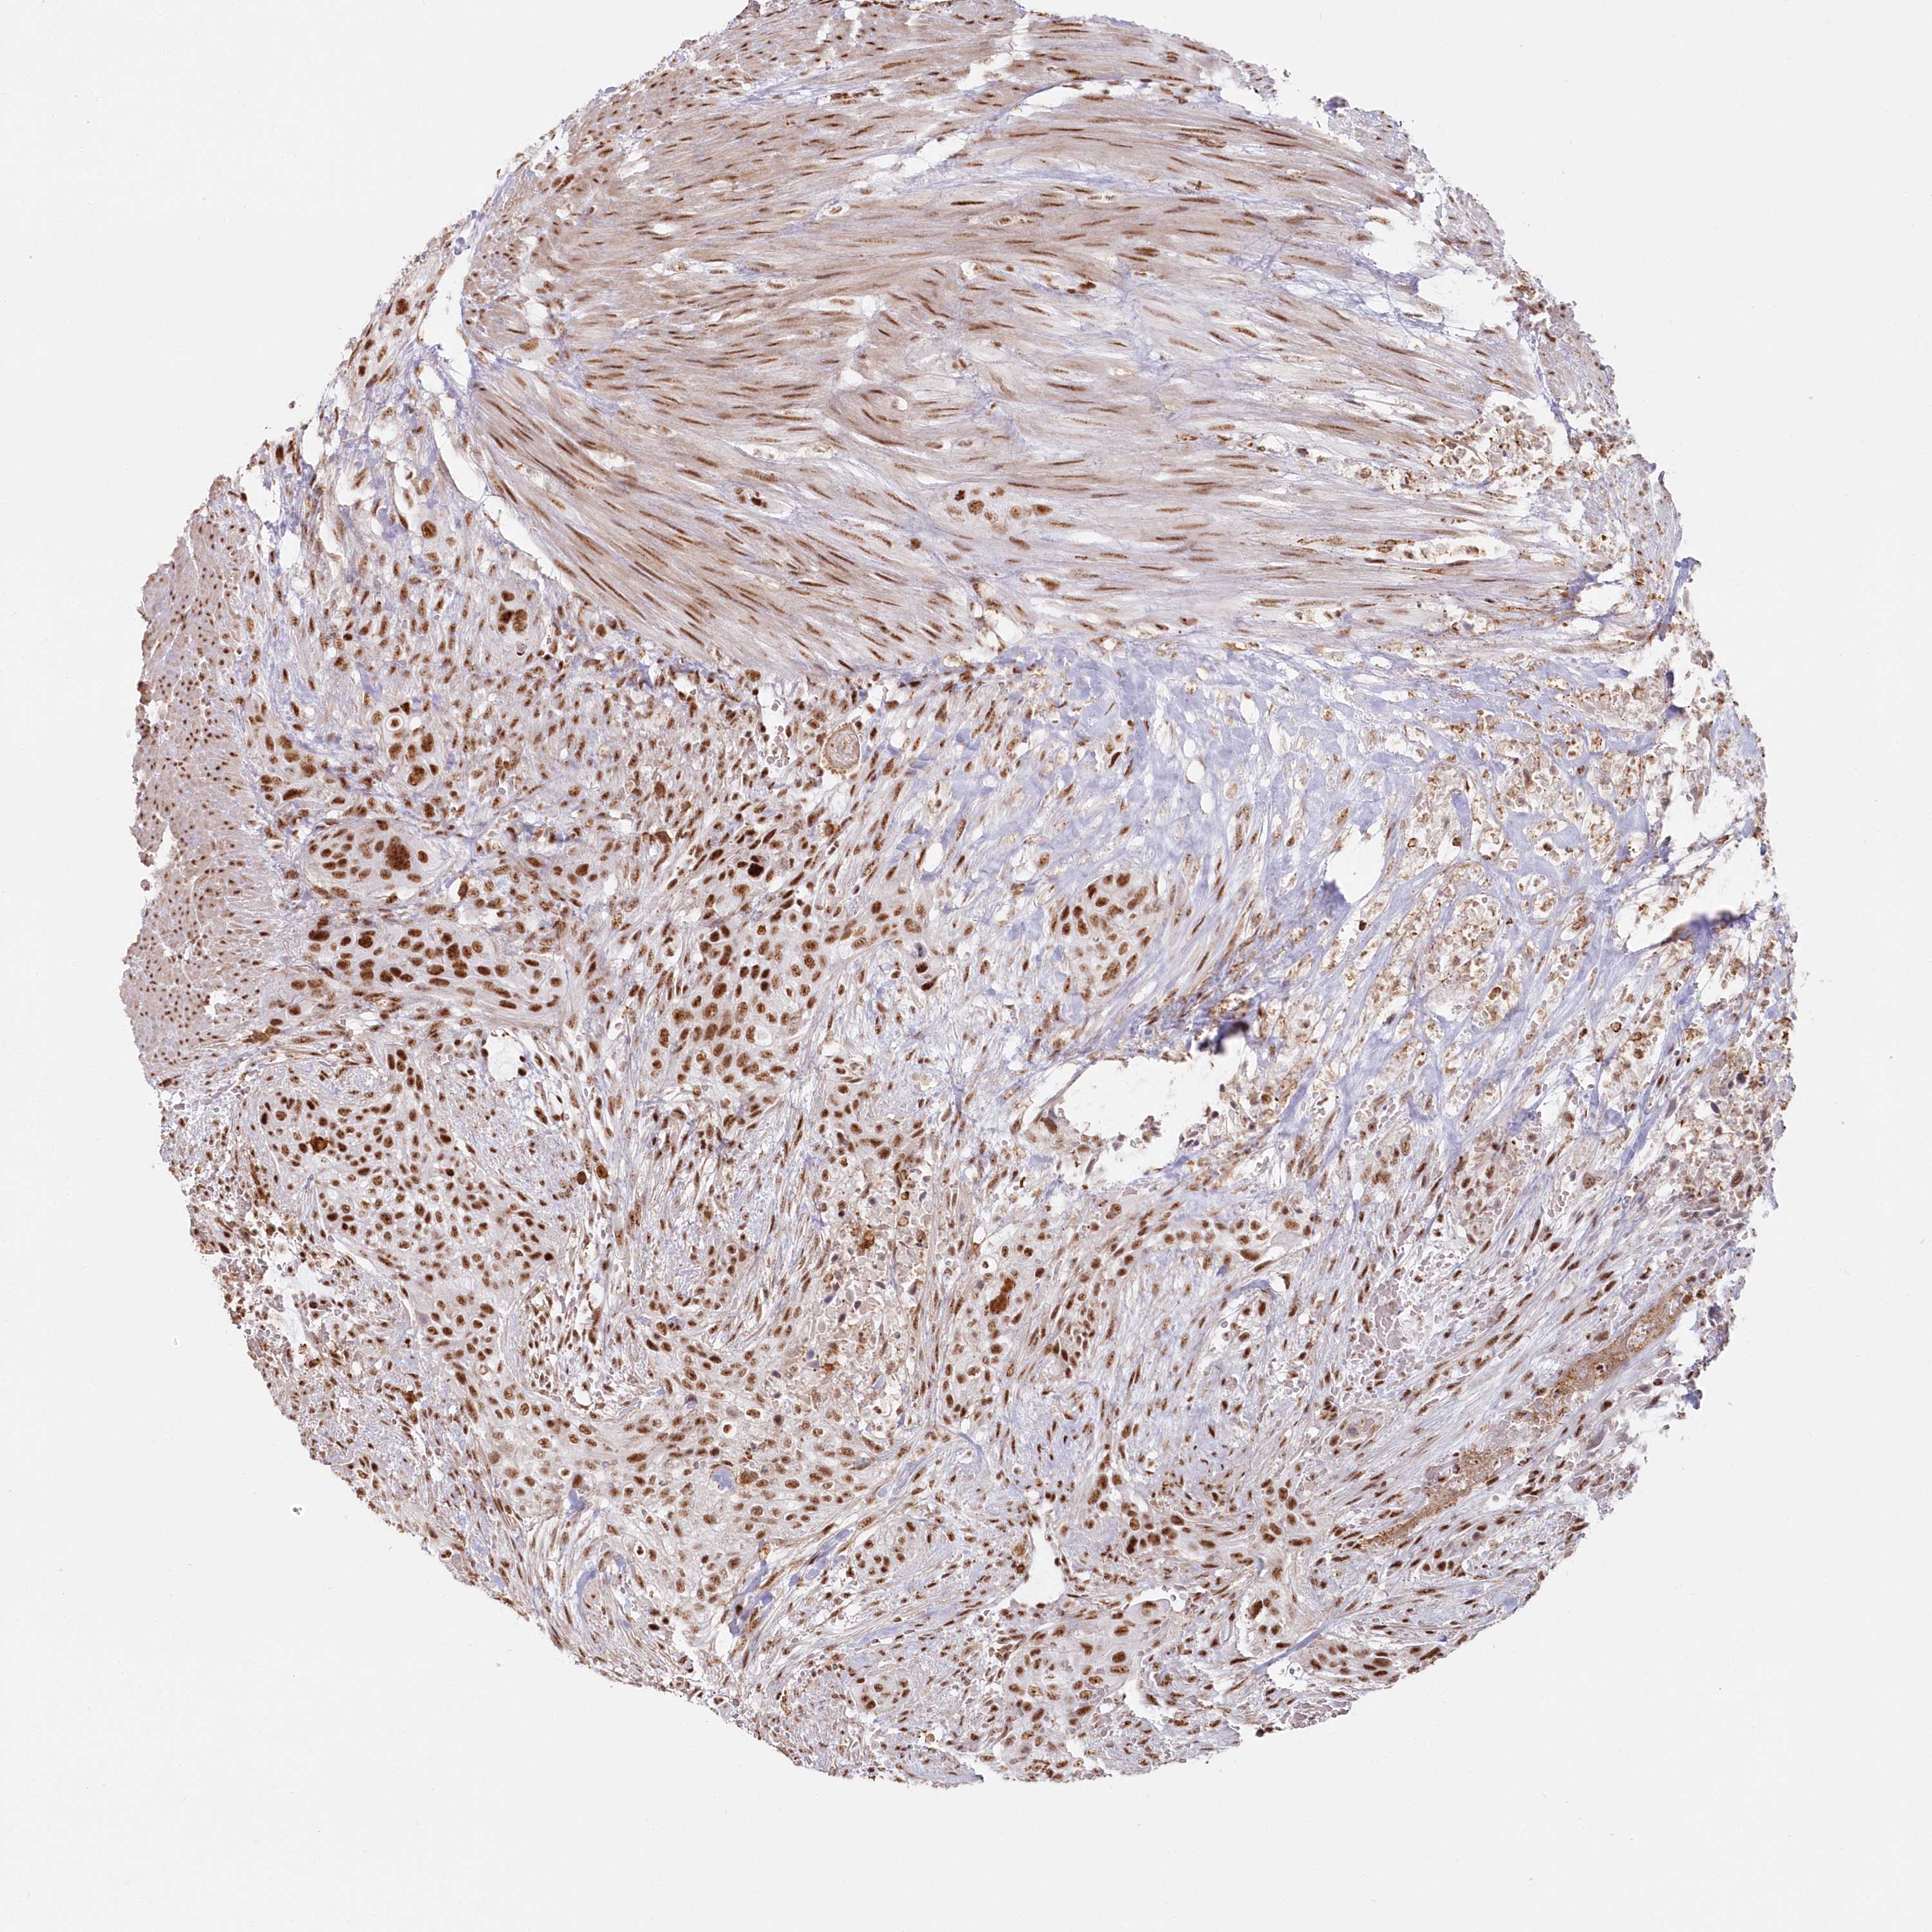

UROTHELIAL CANCER - Protein expressioni

A mouse-over function shows sample information and annotation data. Click on an image to view it in a full screen mode. Samples can be filtered based on level of antibody staining by selecting one or several of the following categories: high, medium, low and not detected. The assay and annotation is described here.

Note that samples used for immunohistochemistry by the Human Protein Atlas do not correspond to samples in the TCGA dataset.

Antibody stainingi

Antibody staining in the annotated cell types in the current human tissue is reported as not detected, low, medium, or high, based on conventional immunohistochemistry profiling in selected tissues. This score is based on the combination of the staining intensity and fraction of stained cells.

Each image is clickable and will lead to virtual microscopy that enables deeper exploration of all samples and also displays staining intensity scores, fraction scores and subcellular localization as well as patient and tissue information for each sample.

Antibody HPA036554

Staining

High

Medium

Low

Not detected

Intensity

Strong

Moderate

Weak

Negative

Quantity

>75%

75%-25%

<25%

None

Location

Nuclear

Cytoplasmic/membranous

Cytoplasmic/membranous,nuclear

Urothelial carcinoma, Low grade

Urothelial carcinoma, High grade